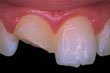

En blivende fortann er slått ut

Sett forsiktig tannen som er slått ut, tilbake på plass og oppsøk straks tannlege.

Tann som er slått ut av kjeven - I mange tilfeller kan tannen settes tilbake i kjeven. Et vellykket resultat avhenger av hvor fort man kan få tannen på plass igjen. Jo lengre tid det går etter at tannen ble slått ut, jo dårligere vil tilstanden til de levende cellene på rotoverflaten være. Legg tannen i melk eller legg den under tungen og oppsøk tannlegen så fort som mulig. Hvis tannen er ren (ikke falt ned på bakken e.l.), kan du selv prøve å sette tannen på plass med en gang. Hold i tannens krone og ikke rør roten. Størst sjanse for et vellykket resultat er hvis tannen settes på plass i løpet av de første 30 minutter etter at tannen er slått ut. Det kan bli nødvendig å rotbehandle tannen på et senere tidspunkt.